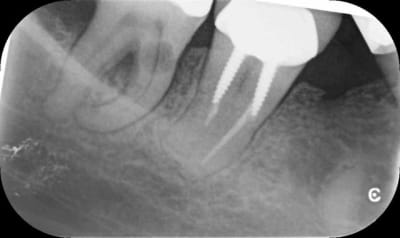

Entre la première et la deuxième radio, tu as clairement un décalage de la lésion.

De plus les contours du canal distal sont très nets sur toutes les radios

On devine une résorption osseuse sur cette racine distale

Donc pour moi tout indique que c'est externe

Finalement oui je révise mon diag et pense à une externe aussi.

Même si je n'en suis pas certain à 100%. On voit bien le canal distal défini en effet derrière la lésion de résorption. Après je pense que les clichés sont décalés ne le sont pas assez pour se faire une meilleure idée mais il semble que la lésion soit décalée entre les clichés 1 et 2 par rapport au canal donc externe aussi.

Je ferai un CBCT pour vérifier le point d'entrée et voir pour la suite.

C'est vrai que mes clichés ne sont pas assez décalés mais j'ai bien examiné la dent et la patiente à un parodontite chronique généralisée. Bref, je pense toujours à une résorption interne, verdict vendredi, à suivre...

J'ai finalement fait faire un cone beam qui a révélé, selon le confrère qui l'a effectué, une lésion externe infra osseuse au niveau mésio-vestibulaire de la racine distale (en inter radiculaire). Dent à extraire selon ce confrère à qui je fais confiance et qui lui aussi n'avait jamais vu çà. Malheureusement, la patiente a gardé le cone beam et est allée prendre un 3eme avis. Je n'ai pas eu de nouvelles mais je voulais vous tenir au courant, merci pour vos avis.